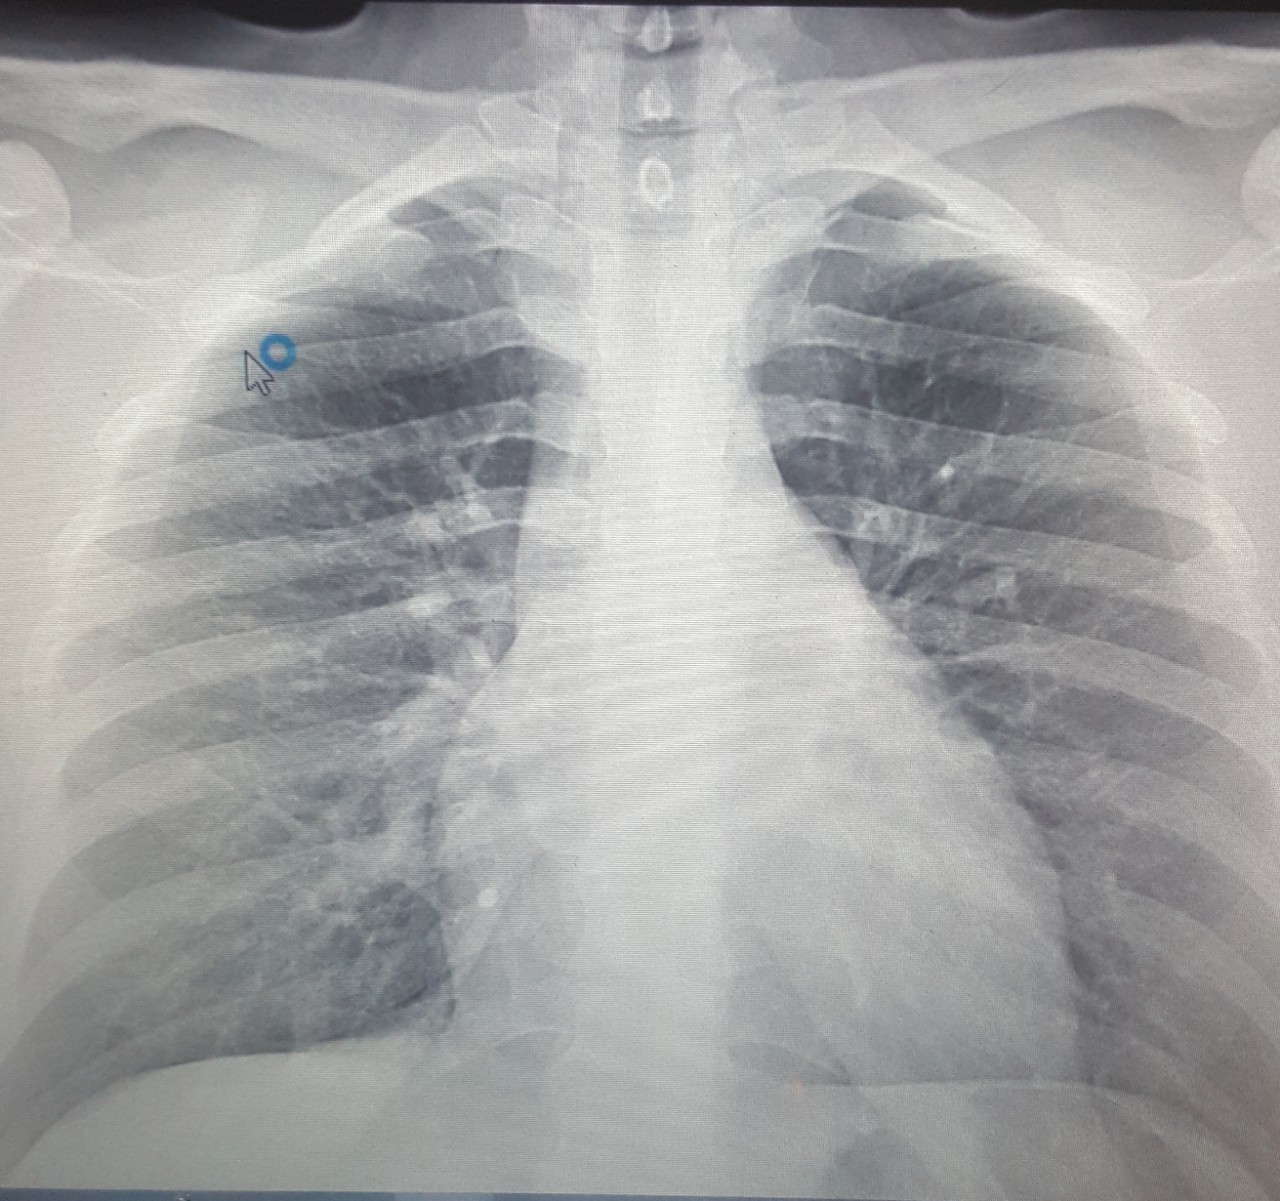

Снимок грудной клетки здорового ребенка: примеры и диагностика

Раздел: Мудрость в объективе